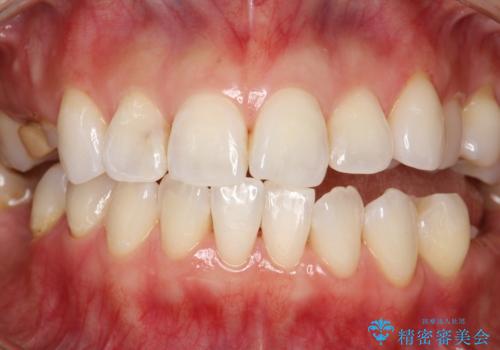

PMTC30分コース(保険外治療)を行いました。かなり久しぶりの歯科医院へ来院とのことで、プラーク(歯垢)・歯石・ステイン(着色)が付着していました。汚れを除去し、本来のご自身の歯質にすることでなにか異常があった際に発見しやすくなります。

PMTCで汚れを除去することは、虫歯や歯周病・口臭予防に効果的です。

また、今回はクリーニング後に、何か所か虫歯や治療途中のままの部分が発見されました。今後は定期的なメンテナンス・クリーニングと併用しながら虫歯の治療を行っていく予定です。